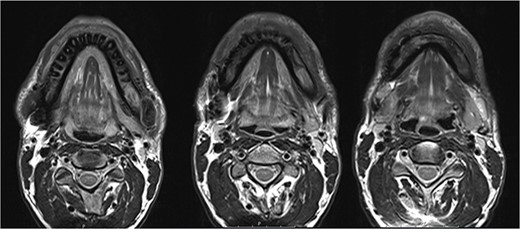

In 2020, a 99 m Technetium scintigraphy was performed to rule out disseminated osteomyelitis. The scintigraphy showed no other foci of enhancement but the mandible with increased inflammatory activity in the anterior portion of the jaw (Fig. 1). Magnetic resonance imaging (MRI) was performed to analyze the localization and extent of the disease. In Fig. 2, a high inflammatory activity, resembled by a strong local enhancement in the T2 weighting, was seen, reaching from the right condyle to the left. Cone beam computed tomography (CBCT) confirmed a widespread patchy radiolucency extending to both left and right mandibular condyles (Fig. 3). Hard tissue biopsies were taken to rule out malignancy due to the disease’s extensive destruction and chronic course. Blood assays were also requested.

Magnetic resonance imaging (MRI) before bisphosphonate therapy (axial sections). T2 weighting of the MRI shows the high inflammatory activity especially in the anterior portion of the mandible (arrow).

The MRI performed three months after the last pamidronate infusion revealed a significant reduction of enhancement in the mandible with some patchy hypointense areas remaining (Fig. 5).

Magnetic resonance imaging (MRI) 3 months after bisphosphonate therapy. T2 weighting shows the significant reduction of inflammatory activity within the mandible after bisphosphonate treatment.